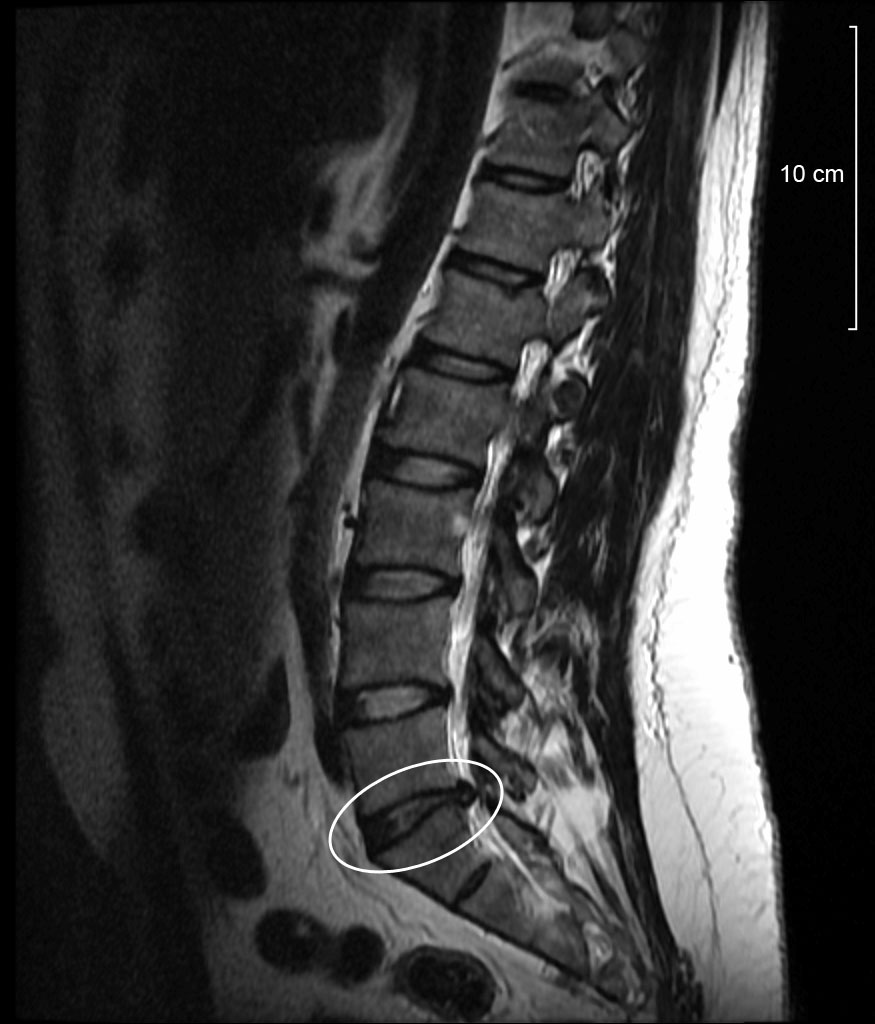

En un estudio publicado recientemente (Herzog, Elgort, Flanders, & Moley, 2017), la misma paciente, una mujer de 63 años, con historia de dolor lumbar y síntomas radiculares L5 en su miembro inferior derecho, visitó 10 centros de imagen diferentes en…